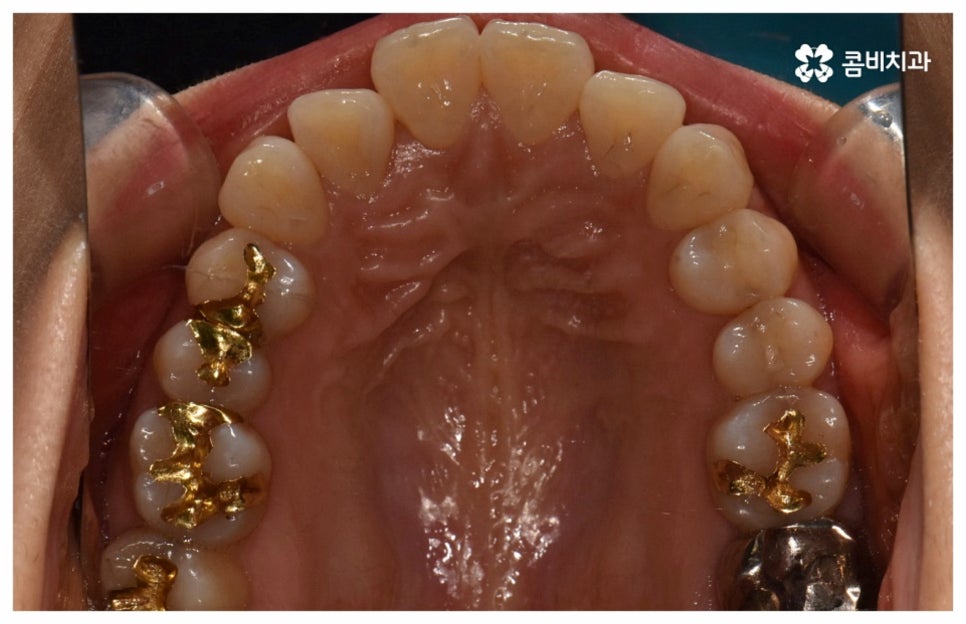

그래서인지 자기 관리의 일환으로 외모를 가꾸고 치아 건강을 증진시키기 위해 중년치아교정 을 고려하시는 분들도 늘어나고 있어요. 치열이 삐뚤어지고 교합이 잘 맞지 않는다면 교정 치료를 통해 이를 바로잡아 저작 기능을 향상시키고 발음을 정확하게 할 수 있으며, 심미적으로도 호감가는 인상을 만들고 추후 치아 관리도 보다 수월하게 할 수 있도록 도움을 받을 수 있기 때문에 이에 대한 수요가 많아지고 있는 거예요.

나이가 들어가면서 치아와 주위 조직들이 약해질 수 있고 치주 질환이 발생할 위험도 높아지기 때문에 중년치아교정 치료시 환자분들의 상황에 따른 맞춤 진료를 더욱 세심하게 진행할 필요가 있어요. 교정 방법이나 주의점에 대해서 꼼꼼하게 확인하고 계획을 세워야 할 뿐 아니라 교정 치료 전에 충치나 잇몸병과 같은 구강 질환이 발견되었다면 이를 미리 깨끗하게 치료하고 진행 과정 중간에도 장치에 음식물 찌꺼기가 끼지 않도록 위생 관리를 철저하게 해주며 치료 후 치아와 잇몸이 약해지지 않도록 환자분들 각각의 치아 이동 속도에 따라 무리하지 않는 것이 중요한 포인트라고 할 수 있습니다.

이와 같이 자연스러운 노화로 인한 변화를 주의깊게 신경쓰면서 충분한 시간을 들여 치아를 이동시키는, 다양한 임상 경험이 풍부한 숙련된 의료진이 처음부터 끝까지 세심하게 케어하는 치과에서 함께 하신다면 중년치아교정 치료를 받는 것을 크게 걱정하실 필요는 없을 거예요. 또한 요즘은 정기 검진 및 스케일링 치료와 같은 평상시 관리의 중요성에 대해 정확하게 인지하고 이를 꾸준하게 해주시는 분들이 늘어나 전반적으로 구강 건강 상태의 양호도가 상향되었기 때문에 40~50대 중년치아교정 치료를 받으시는 데 별 무리가 없는 경우가 많으니 ‘이 나이에 교정은 안될 거다’ 라고 지레 포기하지 마시고 검진과 상담부터 차근차근 받아보시길 권유드리고 있어요.